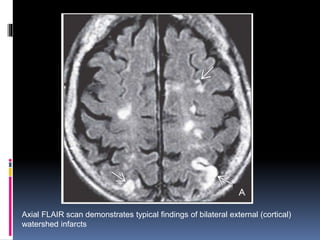

Axial FLAIR scan demonstrates typical findings of bilateral external (cortical)

watershed infarcts

Nearly symmetric confluent and punctate deep white matter hyperintensities

are seen above and behind the lateral ventricles .

FLAIR scan just above the previous image shows distinct bilateral rosary-like

white matter hyperintensities

Axial FLAIR scandemonstrates typical findings of bilateral external (cortical) watershed infarcts

• 50.

Nearly symmetric confluentand punctate deep white matter hyperintensities are seen above and behind the lateral ventricles . FLAIR scan just above the previous image shows distinct bilateral rosary-like white matter hyperintensities